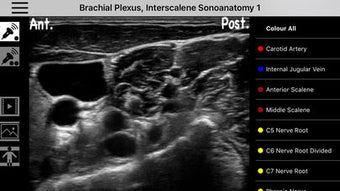

AnSo Anestesia Sonoanatomía es una aplicación para iPhone que proporciona una comprensión integral de la sonoanatomía relevante para el anestesista. Con más de 250 imágenes de ultrasonido y 1500 superposiciones de color de sonoanatomía, esta aplicación es un recurso conveniente diseñado para ayudar a los anestesistas a identificar la sonoanatomía común de manera eficiente en el tiempo dentro del ajetreado quirófano. Creado por anestesistas en ejercicio con interés en la enseñanza de la ecografía y la anestesia regional, AnSo proporciona múltiples ejemplos de la sonoanatomía ya que cada individuo es diferente.